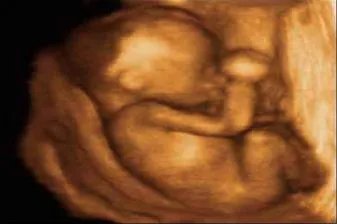

胎儿的四维彩超图片

的有关信息介绍如下:概述四维彩超是在三维彩超的基础上加上时间维作为参数,可以观察到胎儿的实时动态图像,四维彩超的最佳时间在孕20-26周之间。主要方式通过分段检查法,对胎儿器官进行详细检查。1.胎儿头部在双顶平面上测量侧脑室宽度、双顶径和头围,在小脑平面上测量小脑横径、后颅窝池宽度和颈部软组织厚度,观察头颅的完整性。2.胎儿面部观察双侧眼眶、双侧鼻孔、上唇的连续性。3.胎儿胸部观察心脏、肺等胸部结构,心脏要求四腔心脏,左心室流出道,右心室流出道,三血管平面和短轴平面。4.胎儿四肢观察双侧股骨、胫骨、腓骨、肱骨、尺骨和桡骨,测量股骨和肱骨长度,观察双侧踝关节和腕关节。5.胎儿脊柱观察椎体形态、组成结构、及表面皮肤的完整性。